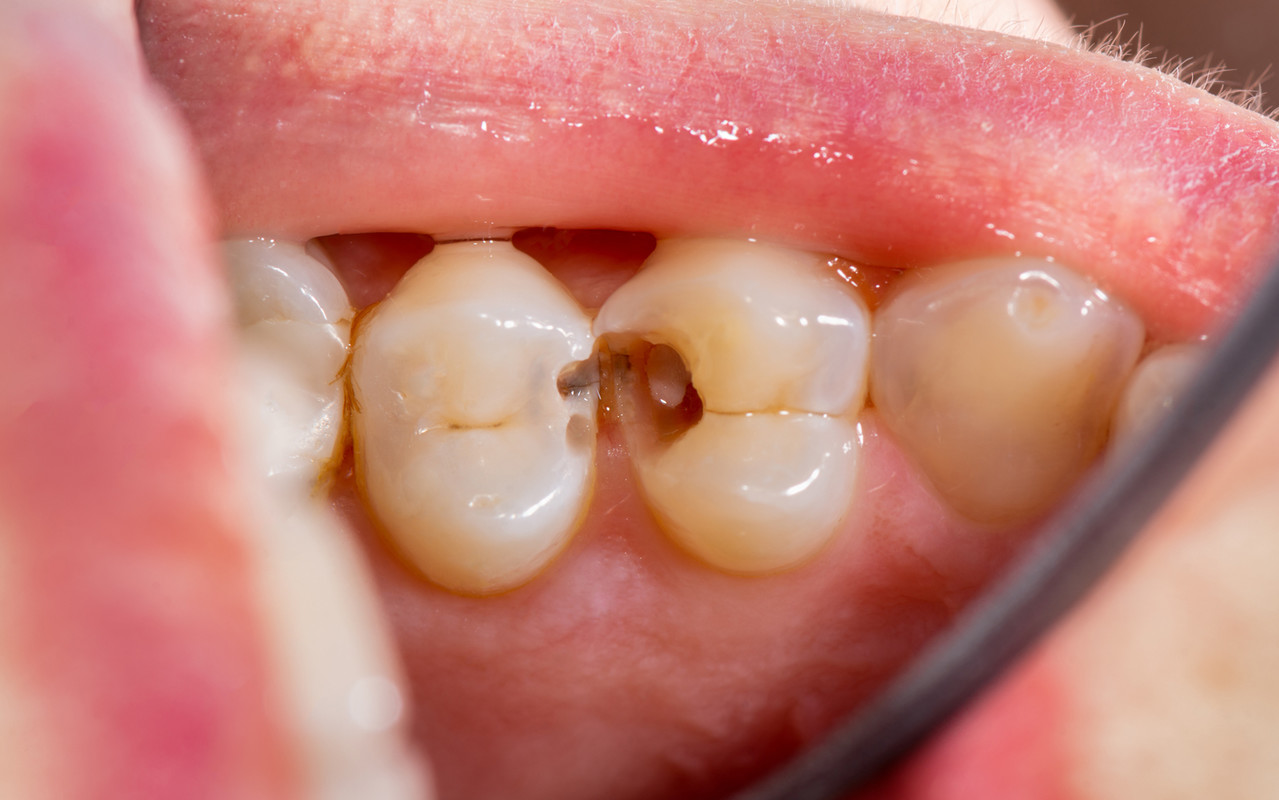

STEP 03. 충치 3단계

증상 : 충치가 신경까지 침범한 단계입니다.

가만히 있어도 욱신거리고, 잠을 설치는

심한 통증이 있을 수 있습니다.

치료 : 충치에 감염된 신경을 제거해 통증을 없애고,

약해진 치아를 크라운으로 보호합니다.

증상 : 충치가 신경까지 침범한 단계입니다. 가만히 있어도

욱신거리고, 잠을 설치는 심한 통증이 있을 수 있습니다.